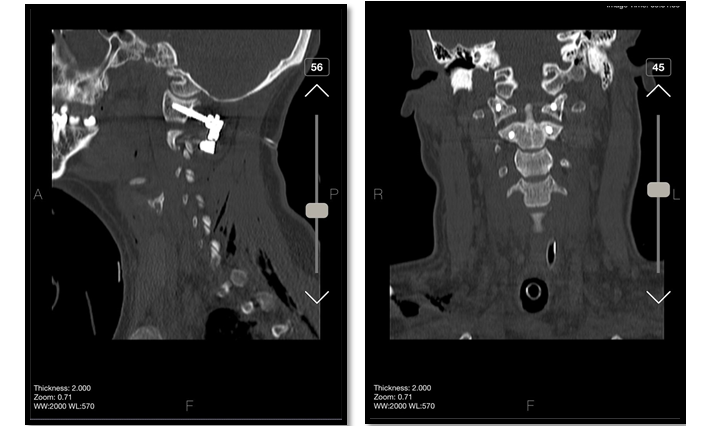

Under general anesthesia, the patient was placed in the supine position. Under fluoroscopy guide and C-ARM imaging monitoring, several times of closed reductions were attempted through gradual manual cranial traction from flexion to extension (Figure-2). To sum up the surgery process; we can say that three phases were done, first of all, the flexion of the head and neck with traction was done, then neutral position applied when the odontoid process was near the posterior wall of the anterior C1 arch. During the process, the odontoid process was locked in the inferior of the anterior C1 arch. Therefore, in the 3rd phase, we decided to push back the odontoid process by using an impactor (Figure-3) through the retro pharynx. The maneuver was successful, and the odontoid was placed in its position. All phases were done under neuromonitoring. Then, He was positioned from supine to prone to fix the C1 and C2 vertebrae. We exposed the axis and atlas surgically via a posterior approach. The attempts to relocate the normal axis-atlas alignment to fuse the facet joints failed. The lateral mass screw was applied for C1, and pedicular 24*8 mm in the right part of C2 and 26*8 mm in the left one was used. The fusion was applied to reduce the ligament injuries (Figure-4 and 5).

Figure 5. post-operative CT images show Lateral mass screw was applied for C1, and a pedicular measuring 24*8 mm in the right part of C2 and 26*4 mm in the left one were used. The fusion was applied to reduce ligament injuries